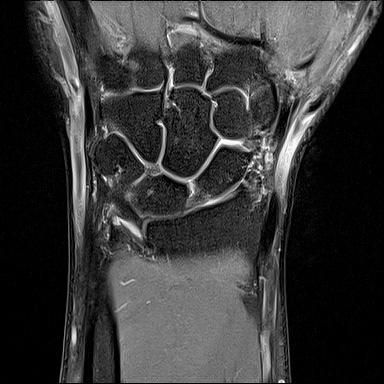

mri는 23년 부분파열 당시

• 4번 째 사진

• 제공해 주신 영상들을 확인했습니다. MRI는 2023년 부분파열 당시 촬영본이고, 단순 방사선 및 CT는 2025년 12월 골절 당시 영상으로 이해하고 검토하겠습니다.

2023년 MRI 영상을 보면, 삼각섬유연골복합체(Triangular Fibrocartilage Complex, TFCC)에 전반적인 신호 변화와 함께 척골 부착부 근처의 손상 소견이 확인됩니다. 당시 봉합술을 시행한 것은 임상적으로 타당한 판단이었습니다. 이후 경과가 양호하다가, 2025년 12월 요골·척골 원위부 골절이 발생한 점이 현재 상황의 핵심입니다.